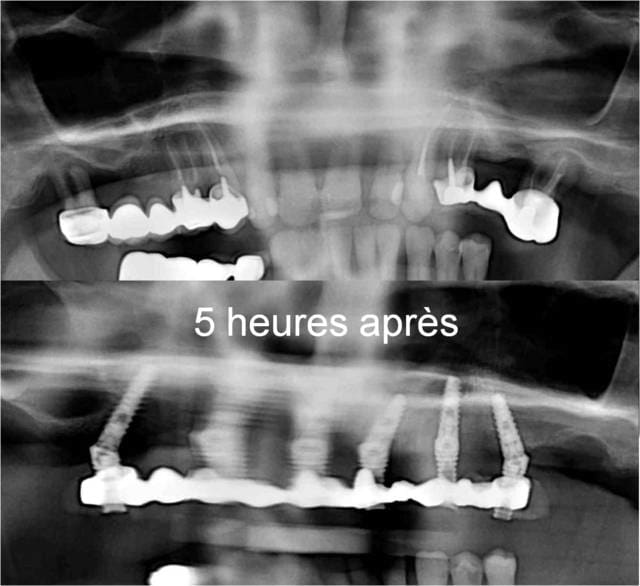

22 KE : 14 implants, 2 sinus lift, 2 pac provisoire, 2 complets sur implants

+ les voyages à repetition ...

Cela aurait été rentable si elle avait eu à faire à un centre d'excellence, car cela aurait pu en etre un : la clinique est ultramoderne selon elle et les patients se bousculent venant d'Autriche, de Suisse, d'Allemagne et d'Angleterre. Dommage que les chirurgiens ne suivent pas ...

NB : les PAC ne sont pas du tout équilibrées, mais stables. Un implant à foiré en secteur 3 et à été remplacé (retiré sans anesthésie, elle a vue les étoiles ...)